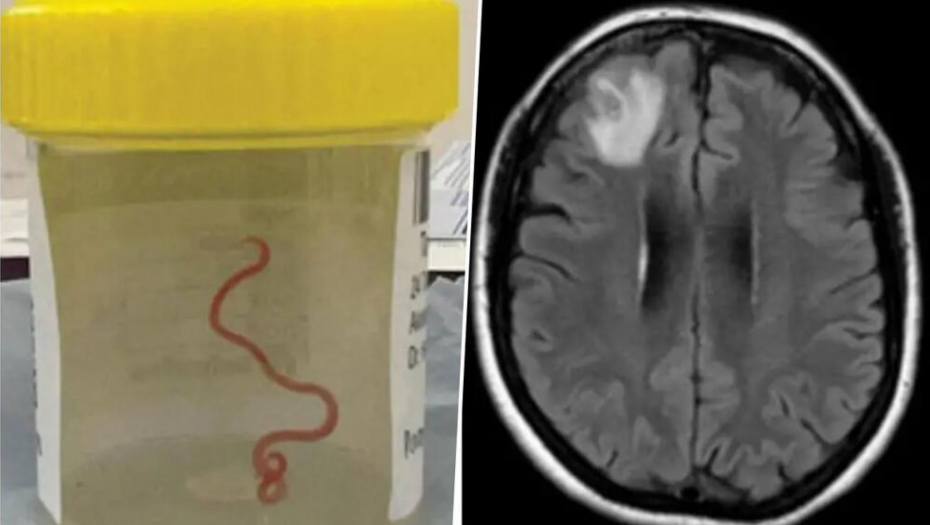

Do 2022. godine njeni simptomi su postali ozbiljni, počela je da zaboravlja i pada u depresiju. Lekari iz male lokalne bolnice uputili su je stručnijim kolegama u Kanberi gde je MRI (magnetna rezonanca mozga) otkrila neke abnormalnosti koje su zahtevale operaciju. Ono što su lekari pronašli u njenom mozgu iznenadilo je čak i njih - živog crva dugačkog 8 centimetara.

- Kanbera je malo mesto, pa smo crva, koji je još bio živ, poslali pravo u laboratoriju naučnika CSIRO-a koji je veoma iskusan sa parazitima. Samo ga je pogledao i rekao: 'O moj Bože, ovo je Ophidascaris robertsi' - prisetio se dr Senanaiake.

Ophidascaris robertsi je okrugli crv koji se obično nalazi kod pitona. Nije baš jasno kako je to dospelo u mozak ove žene, ali činjenica je da ona živi u blizini jezera gde ima pitona.